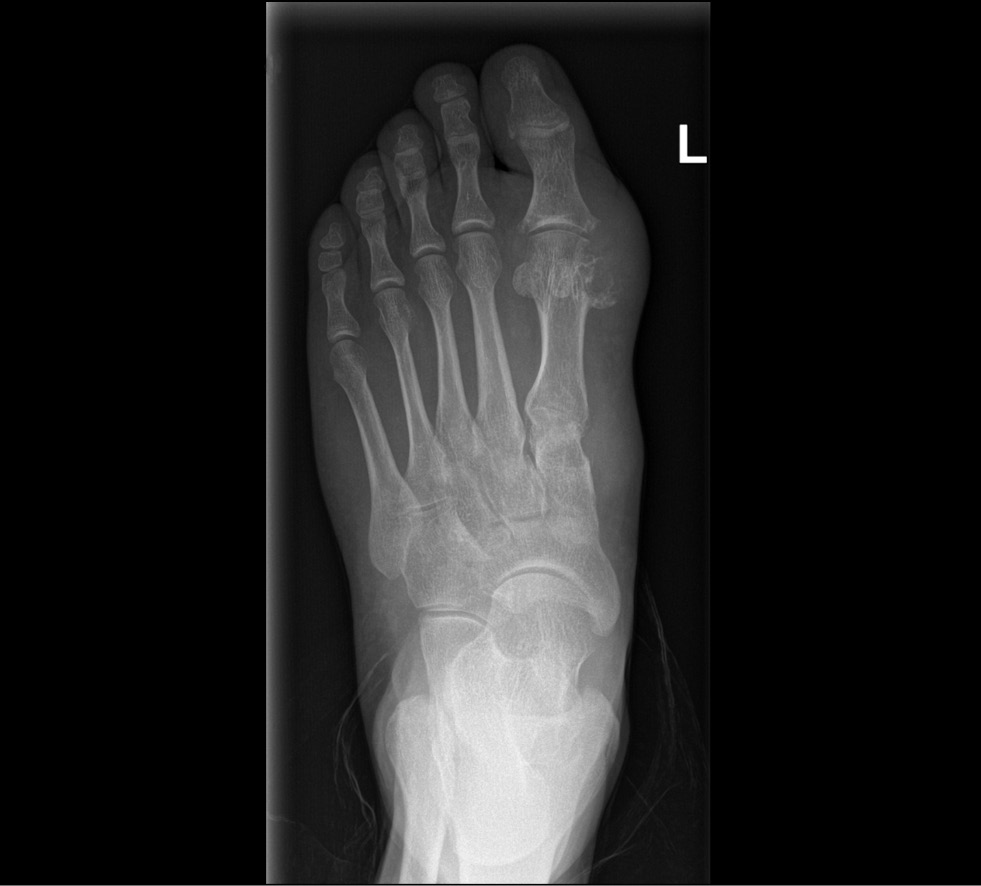

The role of dual-energy computed tomography in the diagnosis of gout and other crystalline arthropathies: A review

Abstract

The importance of dual-energy computed tomography in the diagnosis of gout, the principles of dual-energy computed tomography, the accuracy of the methodology, and the types of artifacts are discussed in this study. The possible dependence of the presence of deposits of sodium monourate on other clinical data and the role of dual-energy computed tomography in the differential diagnosis of other crystalline arthropathies are considered.

The dual-energy computed tomography has several advantages, including noninvasiveness, speed of execution, and a significant reduction in the risk of iatrogenic consequences compared with diagnostic arthrocentesis, which is the gold standard in diagnosing gout. Dual-energy computed tomography can accomplish gout detection, treatment, and differential diagnosis.

197-213